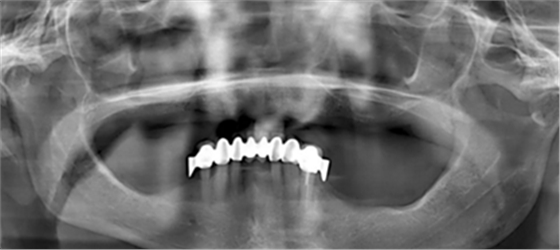

為了最大程度利用現有骨量,需要一個全程引導式的種植外科手術導板。在“以修復為導向”的方案設計過程中,根據CBCT數據,對種植體與基臺中心軸向之間可能的最大夾角進行計算。同時,計劃拔除 21 牙位之前未發(fā)現的殘根。該牙根之所以至今才檢測到,是因為曲面斷層片 (OPG) 上呈現出影像重疊(圖 1)。

(圖1)